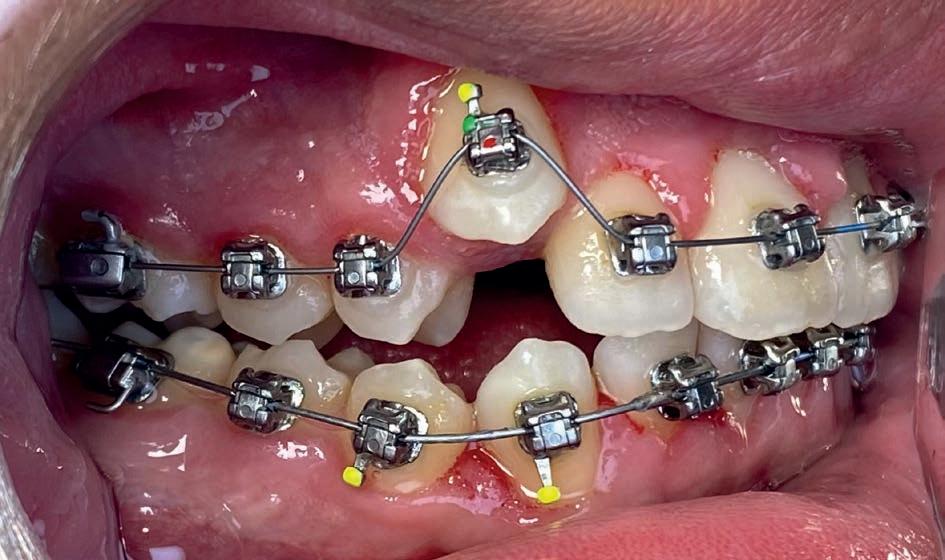

Casus in Proces

Patiënt Sonnie presenteerde zich met ernstig ruimtegebrek ter hoogte van de 13 en 44 en een kruisbeet aan de zijde van de 15 en 14. De 13 was ectostematisch gepositioneerd, waardoor extractie aanvankelijk als mogelijke behandeloptie werd overwogen.

Door een combinatie van verbreding en het inzetten van een D-gainer wordt de benodigde ruimte gecreeerd om alle elementen correct in de tandboog te positioneren, waardoor extracties kunnen worden vermeden. De behandeling zal binnen twee jaar worden afgerond; het eindresultaat wordt gedeeld in editie 2 van ons magazine.

Start behandeling

Midden behandeling

Laatste fase